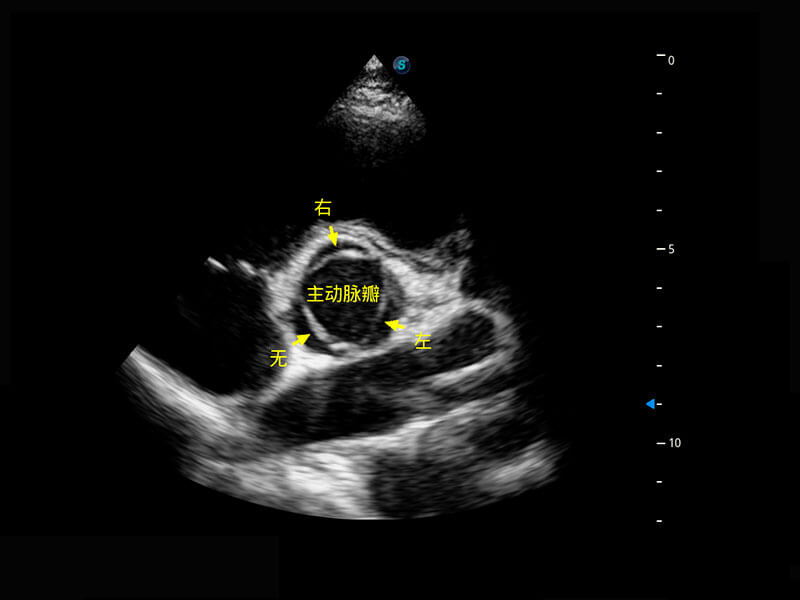

早孕-胎心

P60搭载一系列胎儿心脏成像技术,实现精细的胎儿心脏评估。

四腔切面

四腔心血流

右室双出口

胎心容积成像